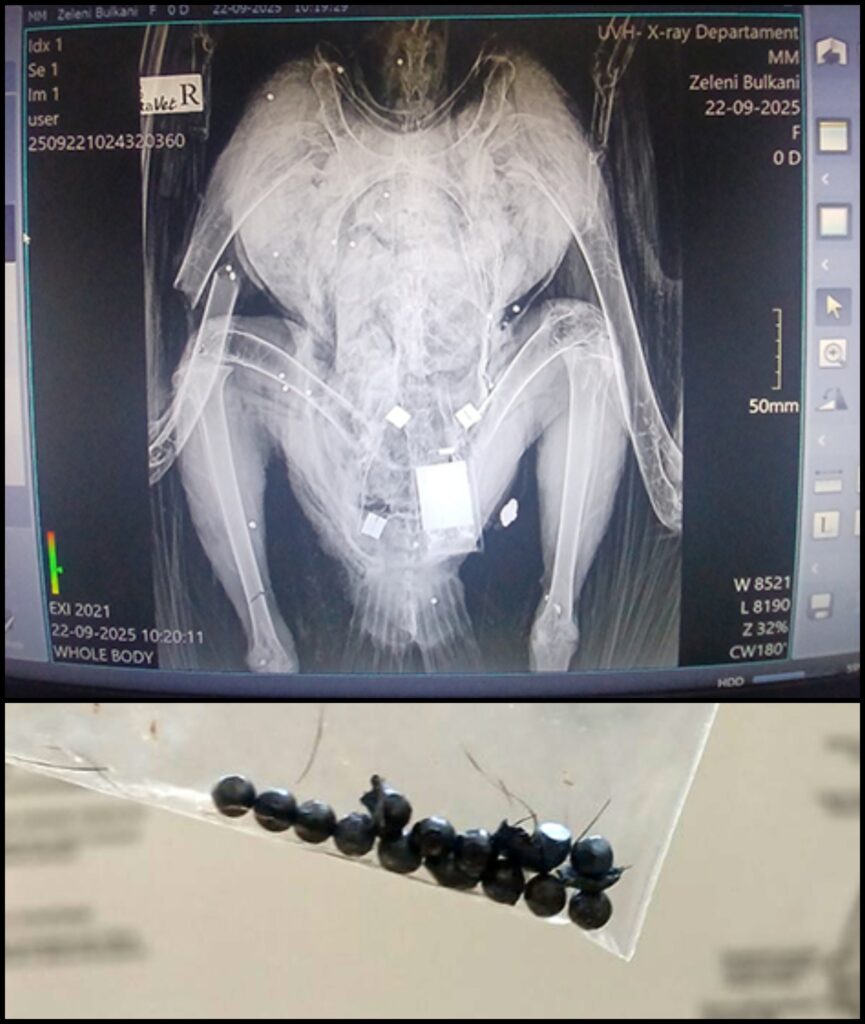

На 20 септември 2025 г. в района на Омуртаг бе прострелян черен лешояд, освободен като част от ключов проект за възстановяване на вида в Стара планина.

Птицата е била част от една от трите успешни двойки, които тази година отгледаха малки в Котленска планина. Това бележеше най-успешния гнездови сезон от началото на програмата през 2018 г. . Смъртта на черния лешояд е сериозен удар за усилията на природозащитниците.